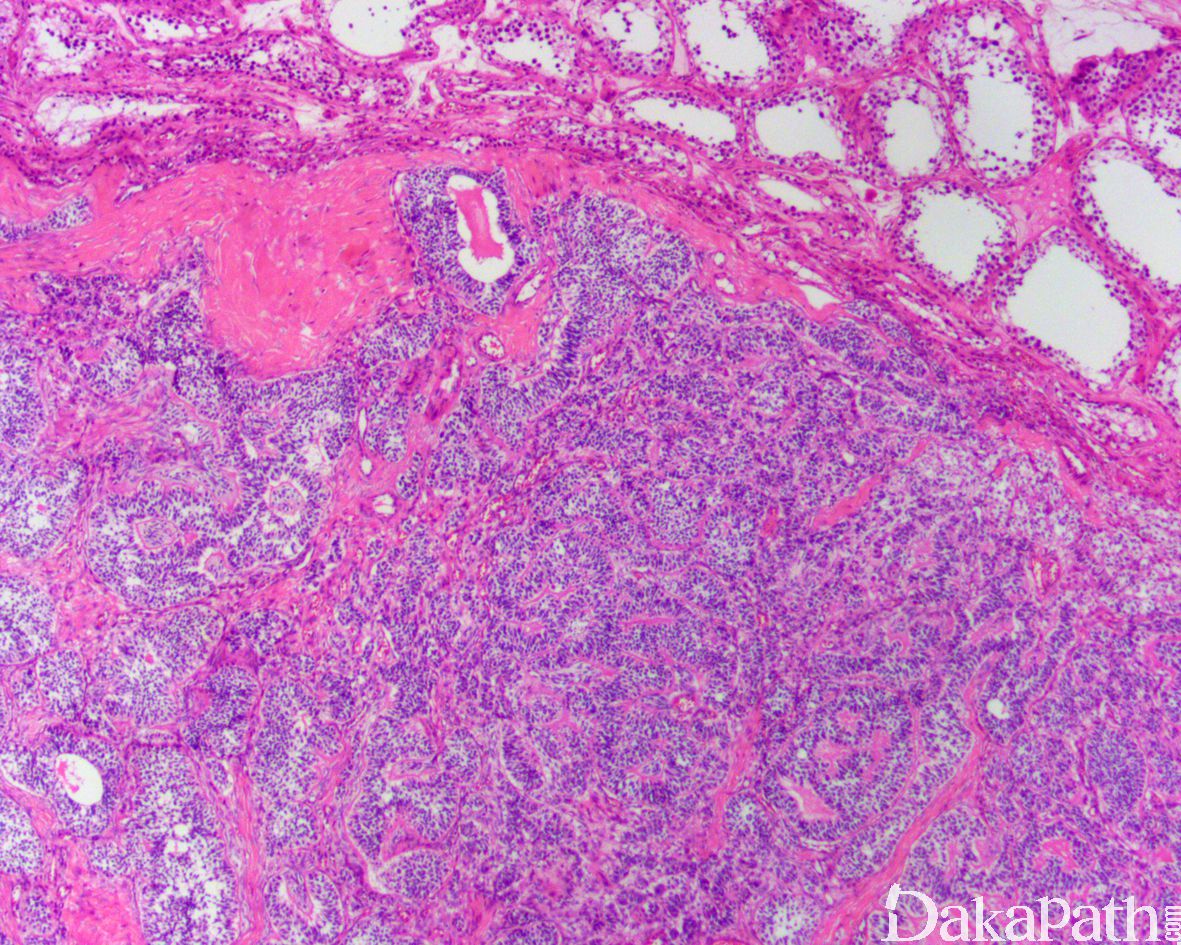

低倍镜下观察,多数病例见管状结构呈结节状分布,间质稀少,少数病例间质丰富;

肿瘤细胞排列成小管,这些管状结构可以呈实性或中央有孔,也可见网状和小管-腺腔结构、索状、束状及单个细胞分布,弥漫性分布少见;小管周围包绕基底膜;

少数病例可见明显淋巴细胞浸润,不要与精原细胞瘤混淆。